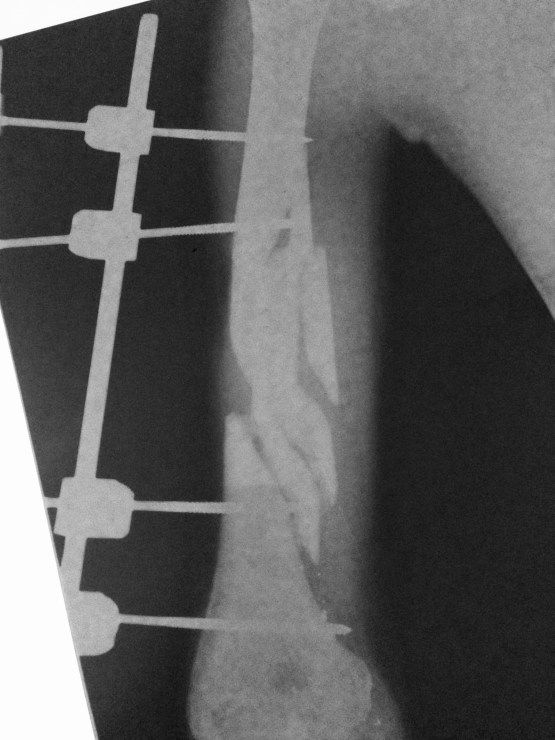

I had another young man (In his 20’s) last week who was shot 8 times, this time by pistol. He was lucky and not so lucky. Lucky in that he was shot 8 times and was still alive. Unlucky in that his injuries were not healing right. And one of the bullets hit him in the eye, so he had lost it (how did he get shot in the eye and not be dead?) His right arm had been broken in a couple places by bullet wounds, and externally pinned back together in a shoddy manner. His lower leg had developed a deep bone infection, called osteomyelitis. He couldn’t walk. He told me that ‘bandits’ had shot him. I’m not sure what the whole story is, but this young man realized what kind of miracle he had on his hands, and was thankful to God. I suggested to him that he must have a significant purpose in this world, for God to pull him through something like this.

At the time of writing this, Dr. Jeff and Dr. Dave have already taken him to surgery to correct the issues with his arm, and clean out the infected wound in his leg. He should make a good recovery.

Humerus gunshot fracture, with external fixation. Can any of my orthopedic friends comment on the pin placement here? It’s just not good…